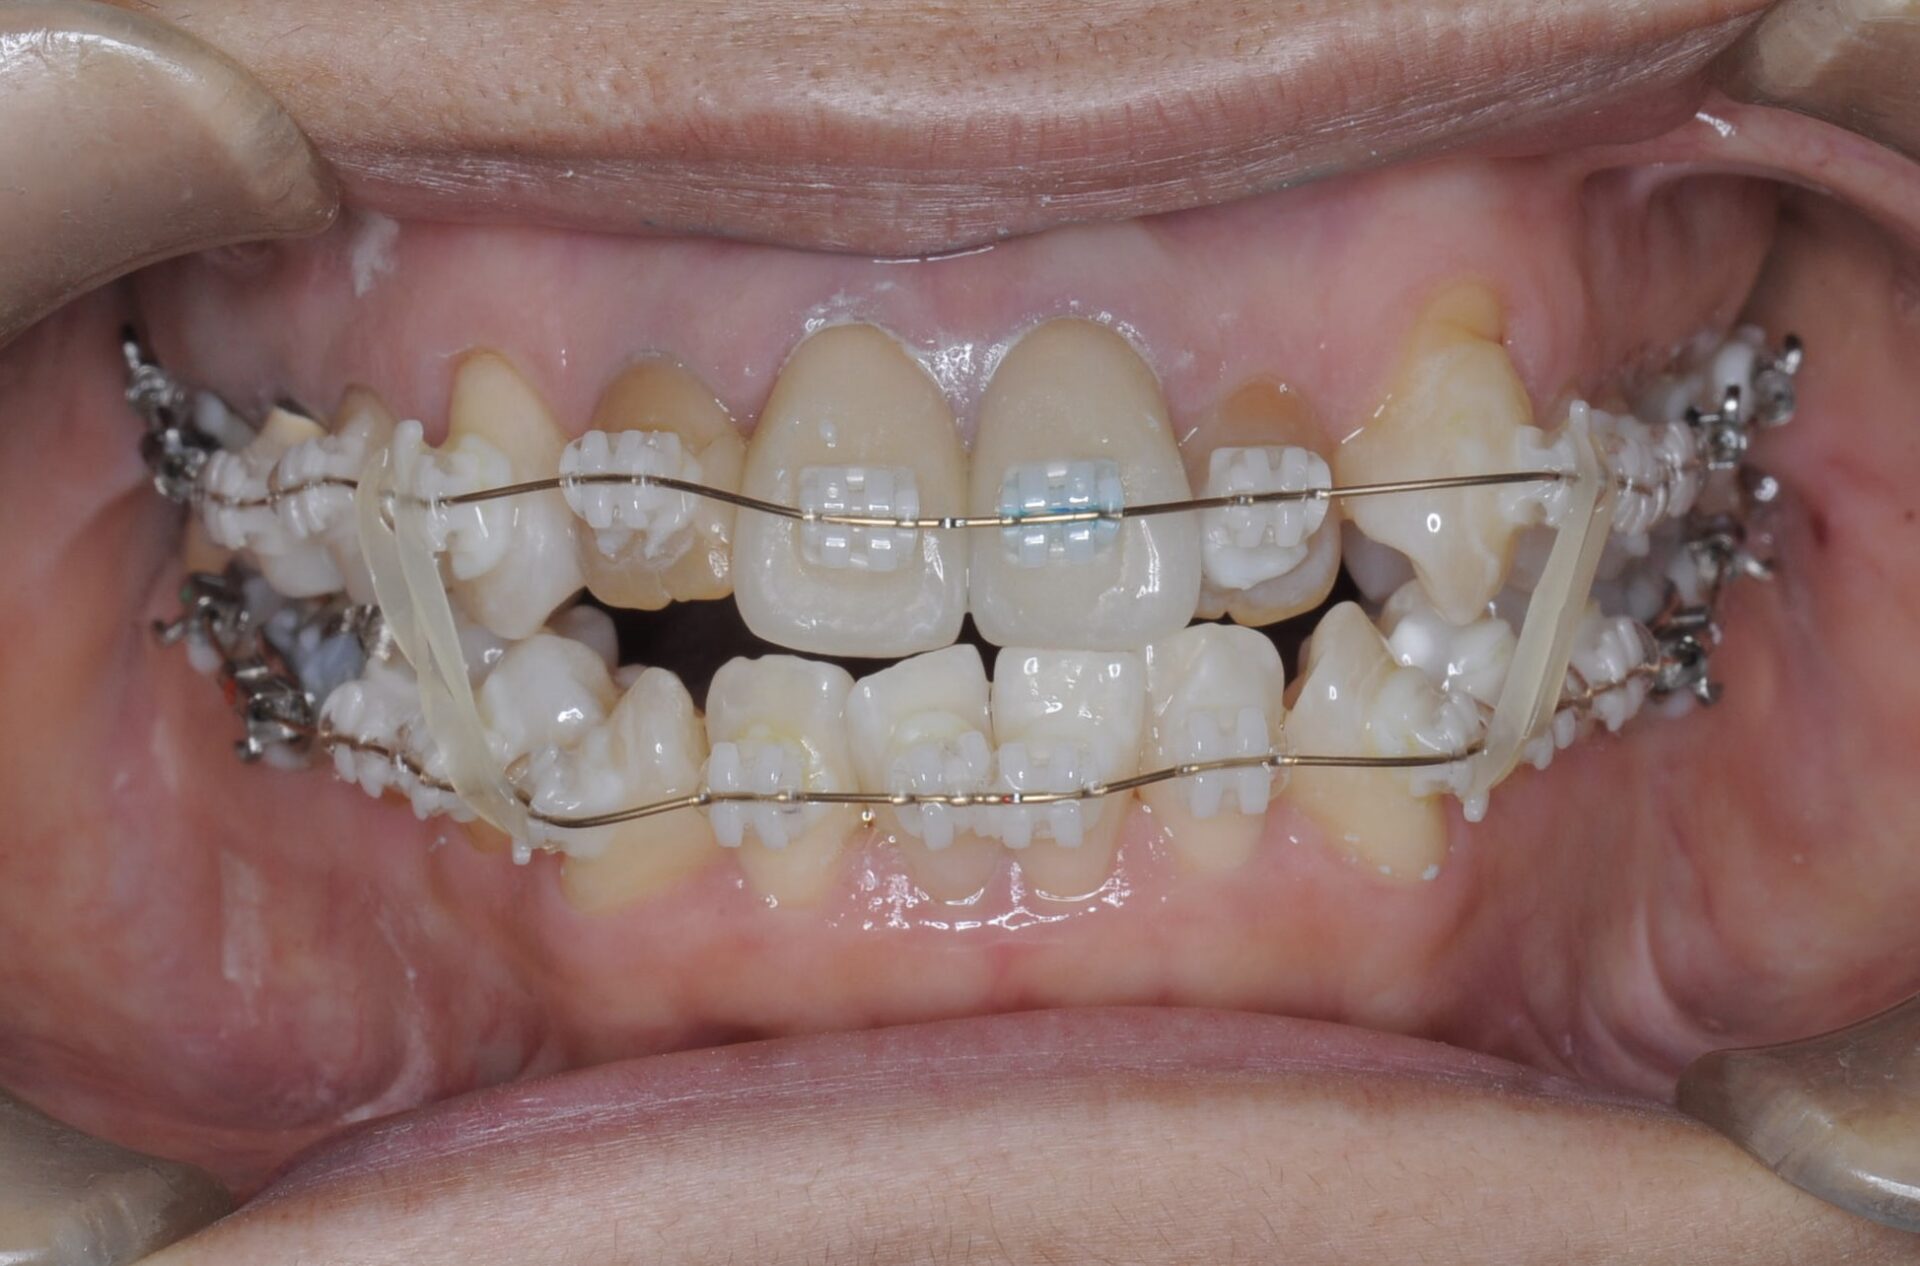

矯正治療スタート(正面)

矯正中